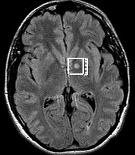

Central Reader Panel